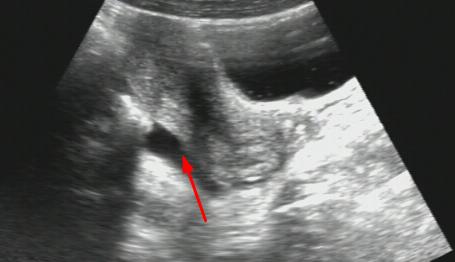

黄体破裂,盆腔大量积血